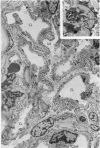

Detailed immunopathologic studies of early or silent renal alterations in systemic lupus erythematosus have been sparse. The renal biopsies of 16 lupus patients with normal renal function, including 8 with hematuria and/or proteinuria of recent onset, and 8 without clinically detectable renal disease were investigated by light, immunofluorescence, and electron microscopy. Immunoglobulins, complement components, and electron-dense deposits were detected in glomeruli of all patients, regardless of morphologic appearance or lack of clinical evidence of renal involvement. Features of membranous glomerulonepritis were observed in 4 patients with substantial proteinuria. In the remaining 12 patients, including 3 with hematuria and 4 with slight proteinuria, either minimal glomerular alterations or features of mesangial proliferative glomerulonephritis were seen. Transformation of the original disease was demonstrated in 3 of 3 patients rebiopsied within 2 years. The significance of these findings is discussed in relation to a) the spectrum of clinical and immunopathologic alterations in lupus nephritis and b) transformation of the original disease.